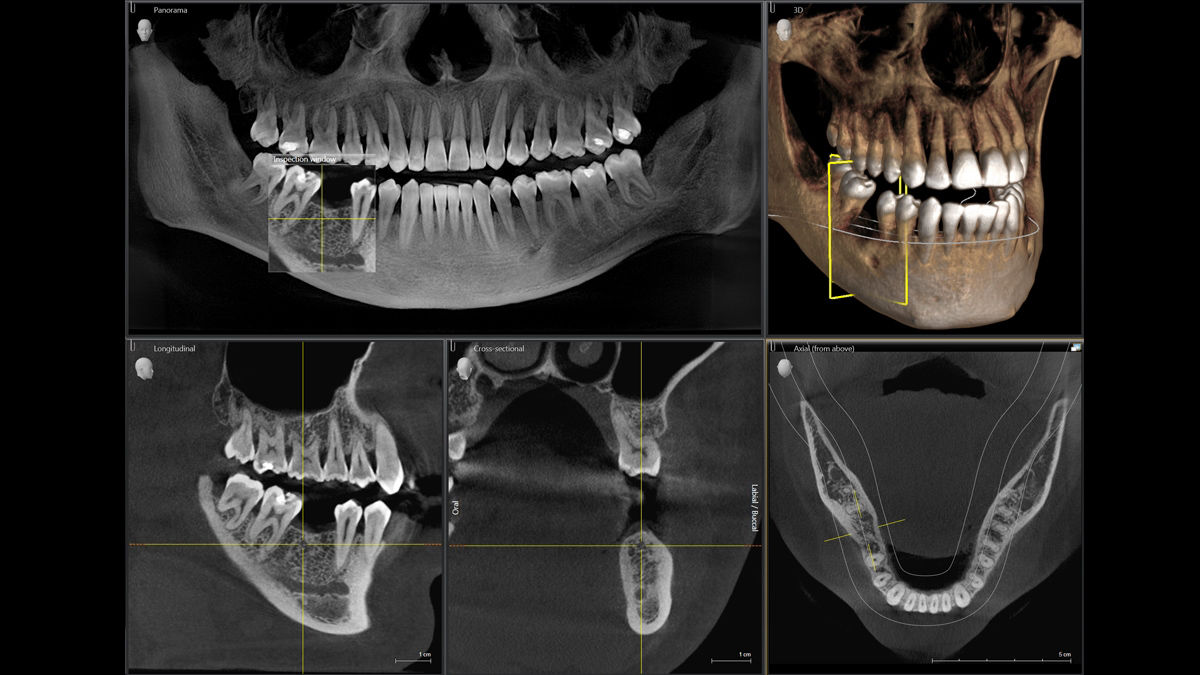

Facescanner

Mientras se obtienen las imágenes DICOM de rayos X, los sensores del Facescanner genera en formato STL la superficie facial del paciente.

El aparato de rayos X y el escáner facial 3D se superponen completamente de forma automática y exacta.

Esta ilustración realista hace que las sugerencias de tratamiento sean más comprensibles para los pacientes  construyendo así una mejor comunicación.